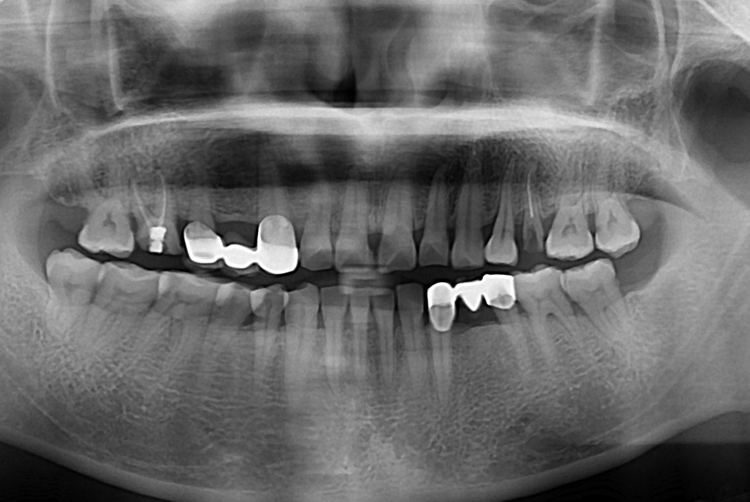

[임플란트] 어금니 임플란트

치료후 : 2018-07-31

세종치과는 많은 환자와 다양한 케이스를 바탕으로

항상 편안한 임플란트 수술을 제공하고자 노력하고,

오래동안 튼튼히 쓸 수 있는 임플란트 수술을 가장 큰 목표로 삼고 있습니다.